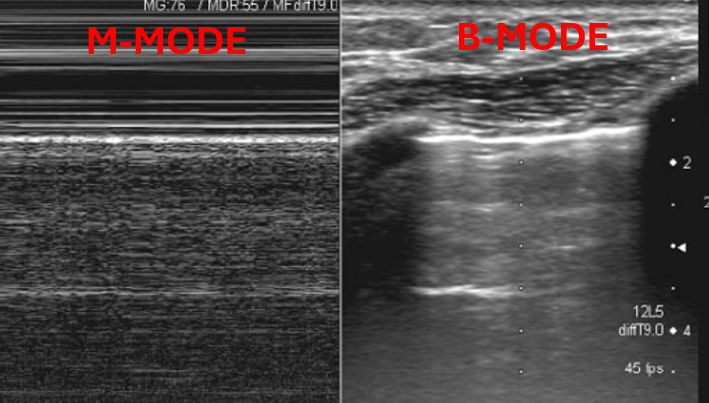

A lines are hyperechoic (ie. bright) horizontal lines that occur equidistant from the pleural line.

A lines are created by repetitive reflections between the pleural line and the ultrasound probe.

The presence of A lines reflects normal lung (ie. lung that does not have pathology such as consolidation, pleural effusion or interstitial syndrome).

B lines are vertical hyperechoic artifacts originating from the pleural line that look similar to comet-tails. The artifact that generates B lines is the ‘ring down’ artifact.